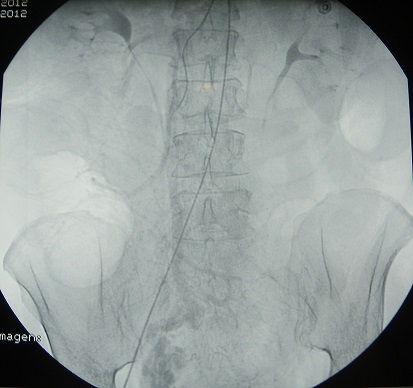

Dados los antecedentes de hepatopatía de la paciente, el deterioro del estado general, la anemización progresiva y la sospecha de variz ileal se decide realizar arteriografía diagnóstico-terapéutica. En la arteriografía, se evidencia la presencia de conglomerado de vasos varicosos a nivel del mesenterio ileal, en íntimo contacto con la pared del intestino, que se rellenan en fase tardía sin extravasación de contraste en el momento de la prueba, por lo tanto sin localización del punto de sangrado (Figura 1).

Figura 1: Conglomerado de vasos varicosos a nivel del mesenterio ileal.